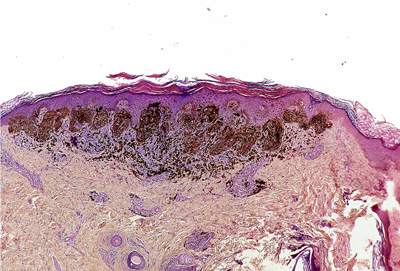

Melanoma - Wikipedia, The Free Encyclopedia

Melanoma, also known as malignant melanoma, is a type of cancer that develops from the pigment-containing cells known as melanocytes. [1] Melanomas typically occur in the skin but may rarely occur in the mouth, intestines, or eye. ... Read Article